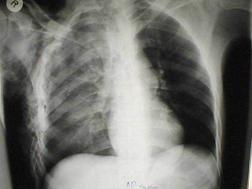

Traumatism toracic deschis Hemotorace stang masiv

Hemotorace stang masiv Hemotorace stang masiv

Hemotorace

drept masiv Hemotorace stang

Imagine CT Radiografie efectuata in ortostatism

Hemotorace drept Hemo-pneumotorace stang

Radiografie efectuata in clinostatism